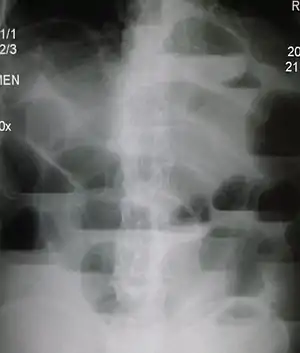

Radiological signs of bowel obstruction include bowel distension and the presence of multiple (more than six) gas-fluid levels on supine and erect abdominal radiographs. Ultrasounds may be as useful as CT scanning to make the diagnosis.[13]

Contrast enema or small bowel series or CT scan can be used to define the level of obstruction, whether the obstruction is partial or complete, and to help define the cause of the obstruction. The appearance of water-soluble contrast in the cecum on an abdominal radiograph within 24 hours of it being given by mouth predicts resolution of an adhesive small bowel obstruction with sensitivity of 97% and specificity of 96%.[14]